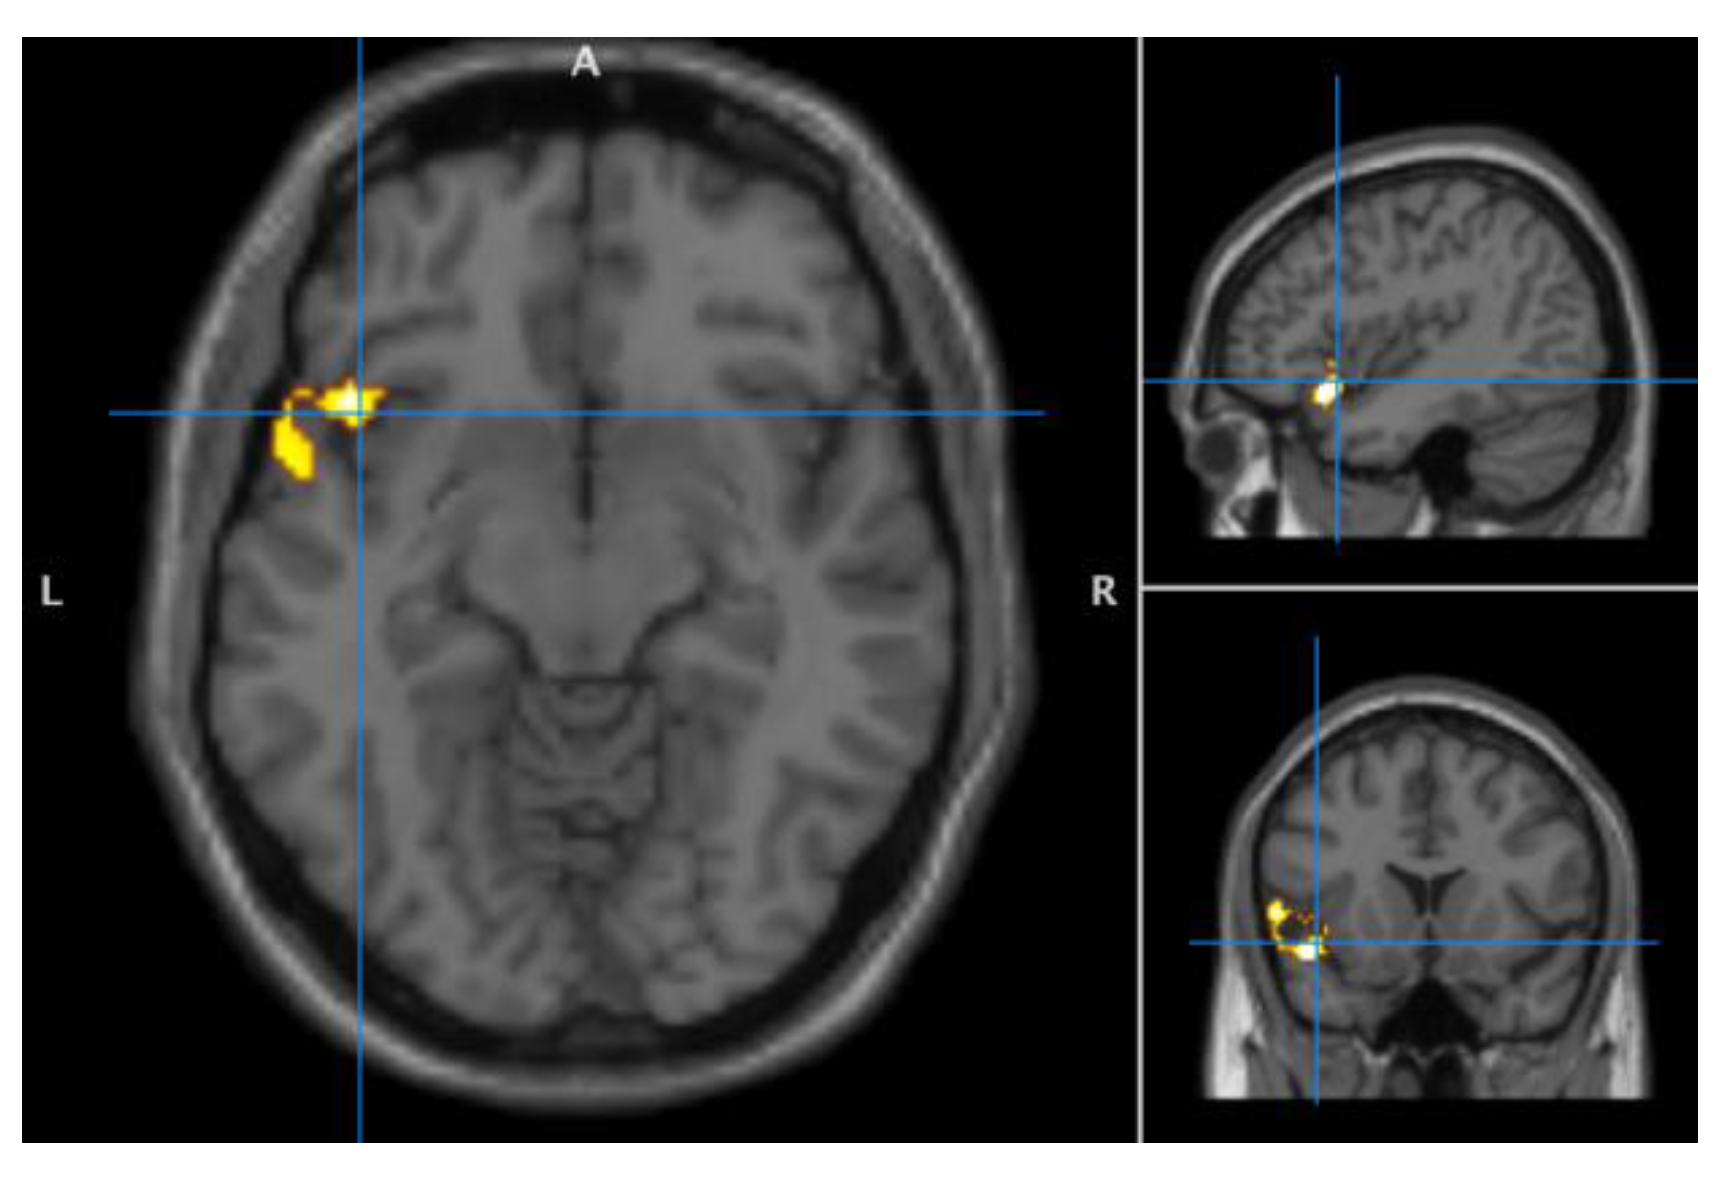

3.2. Seed-Target Tests of between and within-Group Effects

3.3. Exploration of Functional Connectivity ROI to Whole Brain